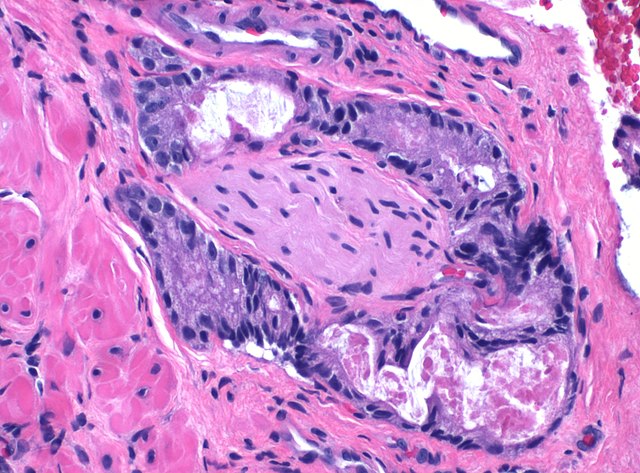

Gastrointestinale Pathologie

Gastritis-Klassifikation und Graduierung, Barrettdiagnostik, Spruediagnostik (modifizierte Marsh-Klassifikation), Beurteilung von Polypen des oberen und unteren Gastrointestinaltraktes mit Diagnostik der intraepithelialen Neoplasie/Dysplasie, leitliniengerechte Aufarbeitung onkologischer Resektate (z. B. Ösophagus, Magen, Darm, Gallenblase, Pankreas) Immunhistochemische MSI-Analyse, Herpesvirus- und CMV-Immunhistochemie In Zusammenarbeit mit Kooperationspartnern MSI-Analyse auf molekularer Ebene, cKIT- Mutationsanalyse, BRAF-Mutationen, KRAS- und NRAS-Mutationsanalysen in Kooperation